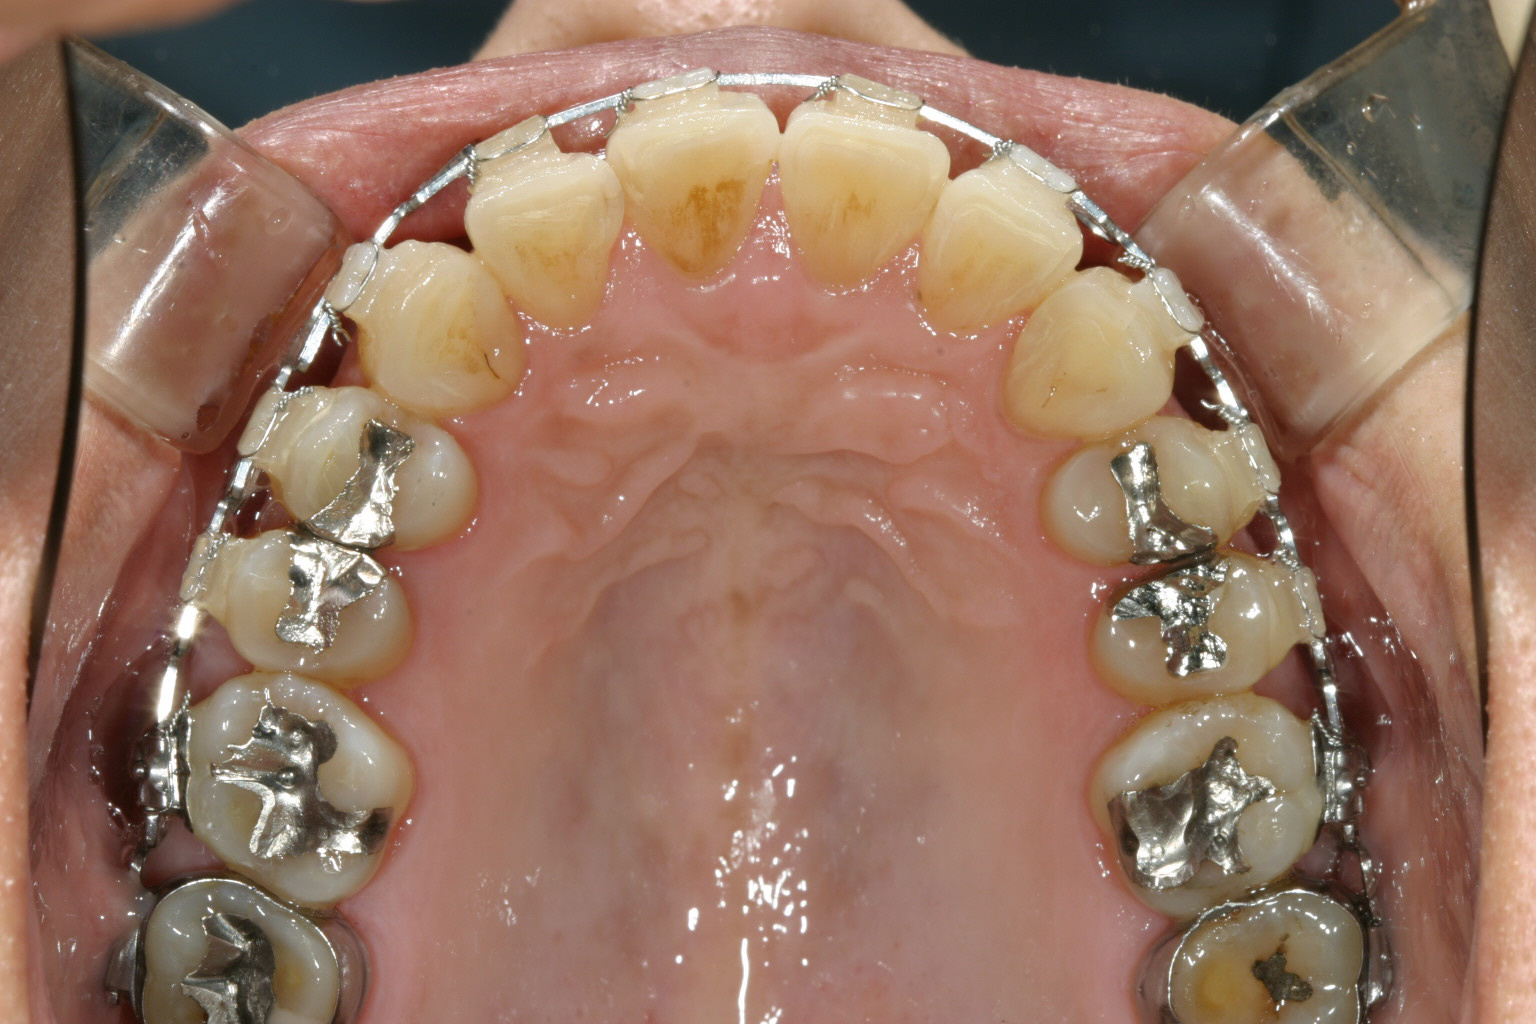

上顎にはさほど乱れを認められません。

左右の臼歯部に高さの誤った冠が被っている為、後にこれを8本入れ替え正常な顎位に変更する。

上顎にマルチループワイヤーを入れアーチフォームを改善する。 アーチフォームもU字変更している。